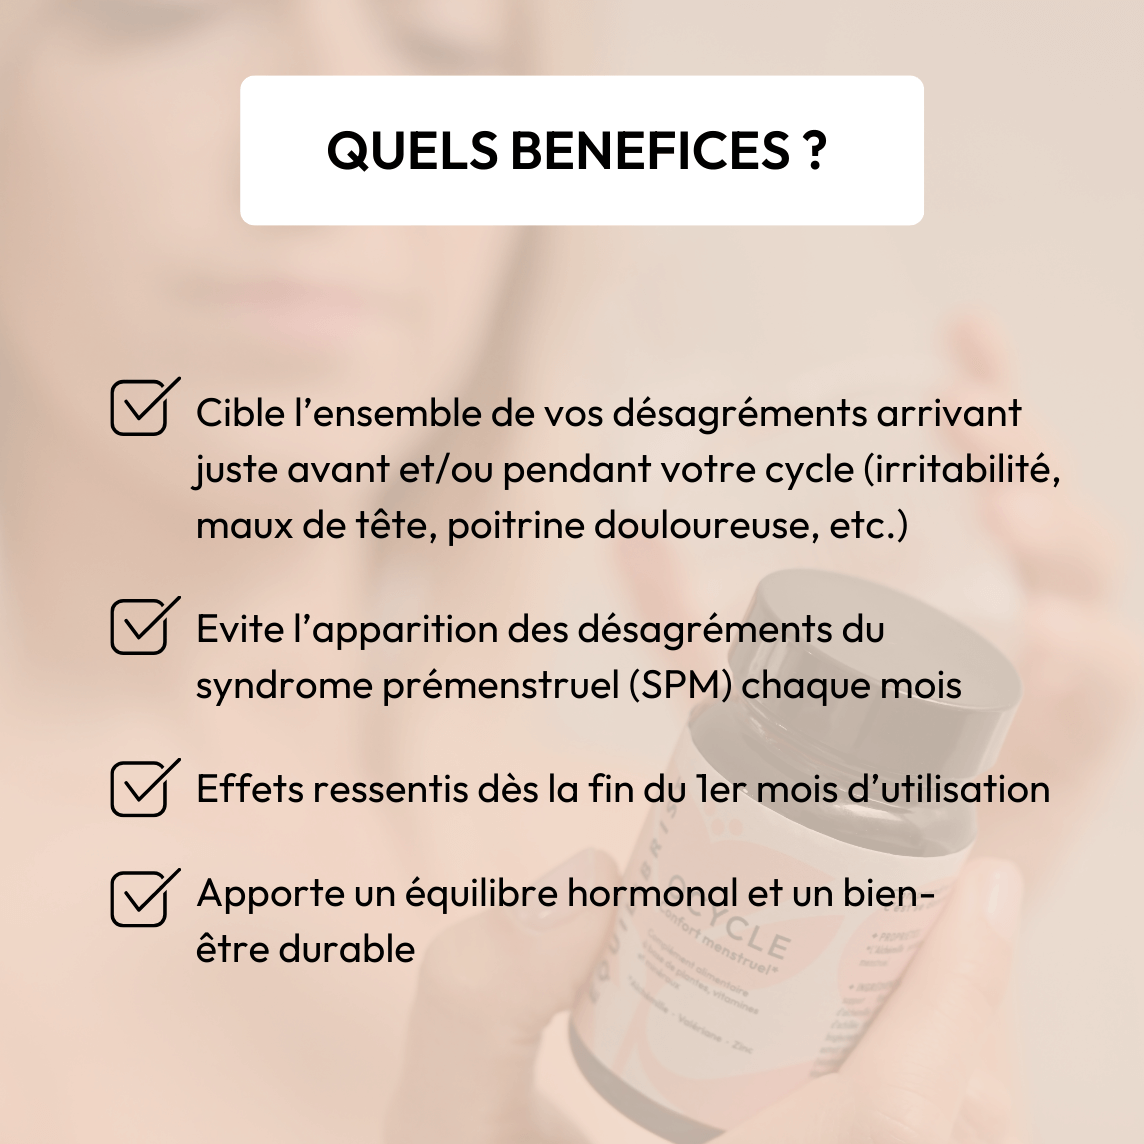

- Réequilibrage hormonal : l’Alchémille & l’Achillée millefeuille augmentent la production de progestérone

- Apport en vitamines & Zinc qui améliorent la régulation hormonale

- Soutien global, décontractant musculaire, antispasmodique & relaxant (Valériane)